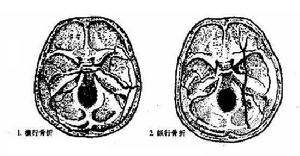

顳骨骨折顱骨骨折多發生於顱底部,1/3的顱底骨折侵入顳骨岩部。依其骨折線分為縱行駛骨折、橫行骨折及岩尖骨折三類。

骨折類型及臨床表現通常以骨折線與岩部長軸的關係,將顳骨骨折分為3種類型:

顳骨骨折2、橫行骨折較少見。約占20%,多由頭顱壓縮性損傷引起。骨折線常起自顱後窩的枕骨大孔,橫過岩錐到顱中窩,有的經過舌下神經孔及岩部的管孔(如頸靜脈孔)、個別的可經內耳道和迷路到破裂孔或棘孔附近,因而骨折線可通過內耳道或骨迷路,還可將鼓室內壁,前庭窗、蝸窗著列,故常有耳蝸、前庭及面神經受孫症狀。如乾音性聾、眩暈、自性眼震、面癱其血鼓室等,面癱的發生率約占50%,且不易恢復。